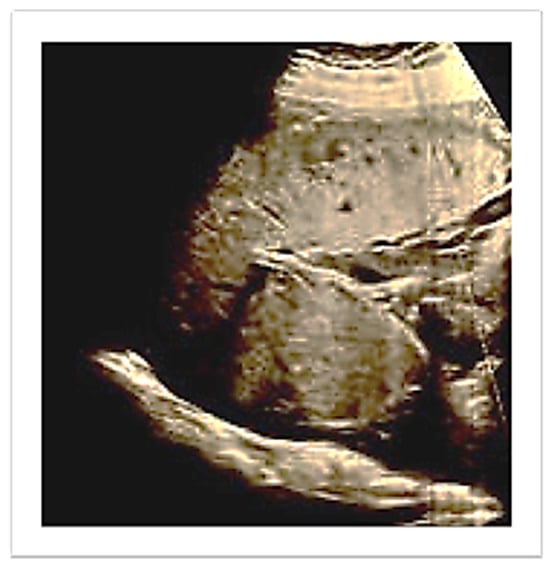

Two consecutive manual removals were attempted, without success. A third one by a senior operator was performed and failed due to a mechanical difficulty at placental extraction. Therefore, given the persistent uterine bleeding, around 600 mL, the administration of Oxytocin (20 IU, 500 mL normal saline, continuous infusion) and Tranexamic acid (1 g, 100 mg/mL) was started. The patient was informed about the need for a surgical treatment; therefore, she underwent a laparotomic exploration. The uterus appeared asymmetrically enlarged, with an irregular right cornual bulge, at the site of the trapped placenta (Figure 3).

Figure 3. Arrow: Uterine irregular bulge, site of the trapped placenta.